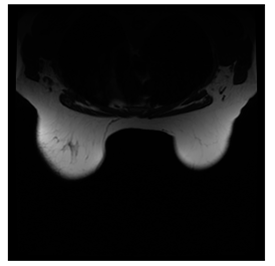

Breast-MRI-NACT-Pilot is an MRI-type image database, collecting breast medical images of 64 patients. Some samples are shown in Figure 12a.

Figure 12.

Sampled images in the tested benchmark databases: (a) Breast-MRI-NACT-Pilot (breast), (b) ACRIN-DSC-MR-Brain (brain), (c) NIH (chest), (d) Lung-PET-CT-Dx (lung), (e) Prostate-MRI (prostate), and (f) Other grayscale standard images.